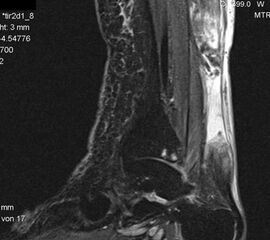

Der geübte Untersucher kann anhand des seitlichen Röntgenbildes die Diagnose einer Achillessehnenruptur stellen. Die Konturen des Kager-Dreiecks – gebildet von der ventralen Begrenzung der Achillessehne, der posterioren Tibiakante und der kranialen Kalkaneuskortikalis – verstreichen im Rupturfall (Kager 1939). Die MRT- Diagnostik spielt für die Primärdiagnostik der frischen Achillessehnenruptur eine untergeordnete Rolle und ist im Normalfall nicht notwendig. Anders verhält es sich bei den chronischen Rupturen. Hier ist die MRT ein wichtiges Diagnostikum insbesondere in Hinblick auf die Beurteilung der Sehnen- und Muskeldegeneration (Abb. 6).

Abbildung 6

Neben der strukturellen Wiederherstellung der Sehne ist die funktionelle Beurteilung des Muskels von entscheidender Bedeutung. Ist es bereits zu einer Degeneration der Muskeln gekommen, kann ein gutes funktionelles Ergebnis, trotz subtiler Sehnenrekonstruktion, nicht erreicht werden. Die Arbeitsgruppe um Hoffmann et al. 13 konnte in ihrer Arbeit zeigen, das es - ähnlich wie bei Patienten mit chronischen Supraspinatusrupturen - zu fettigen Degenerationen und Ödemen der Muskulatur kommt, die im MRT nachweisbar sind. Wir empfehlen die MRT- Untersuchung des gesamten Unterschenkels und nicht nur die rupturnahen Bereiche. Des Weiteren lässt die MRT eine Beurteilung der Degeneration der umliegenden Sehnenanteile zu. Die Computertomographie sollte nur in Ausnahmefällen zum Ausschluss von Begleitverletzungen (Abb. 7) durchgeführt werden und gibt uns sonst keinen weiteren Informationsgewinn.